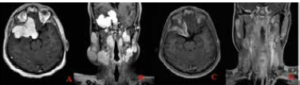

Fig 1) A-B) Axial and coronal T1 and post-contrast images at presentation

revealing the extent of disease, C-D) 12 months post-radiotherapy showing

further interval reduction in size and extent of widespread dural thickening,

with decreased extension, reduced enhancement, and improved mass effect. Follow-up imaging at four months post radiotherapy showed